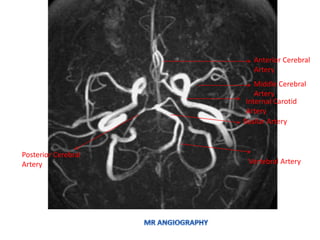

• MR ANGIOGRAPHY / VENOGRAPHY

• Indications :

– Evaluation of cerebral arteries in cases of stroke,

subarachnoid and intracerebral hemorrhage,

trauma, AVM, suspected or known aneurysm etc.

• Sequence:

– 3D TOF(Time of flight ) for circle of willis in the

axial plane

– 3D TOF for vertebrobasilar system in axial plane

– For AVM, additional sequences needed are

– 3D TOF through region of interest

12/20/2017 MRI Brain by Sudil 100

• TWO TYPES OF MR ANGIOGRAPHY

– CE (contrast-enhanced) MRA

– Non-Contrast Enhanced MRA

• TOF (time-of-flight) MRA

• PC (phase contrast) MRA

MR ANGIOGRAPHY

CE (CONTRAST ENHANCED) MRA

 T1-shortening agent, Gadolinium, injected iv as contrast

 Gadolinium reduces T1 relaxation time

 When TR<<T1, minimal signal from background tissues

 Result is increased signal from Gd containing structures

 Faster gradients allow imaging in a single breathhold

 CAN BE USED FOR MRA, MRV

 FASTER (WITHIN SECONDS)

TOF (TIME OF FLIGHT) MRA

 Signal from movement of unsaturated blood converted into

image

 No contrast agent injected

 Motion artifact

 Non-uniform blood signal

 2D TOF- SENSITIVE TO SLOW FLOW – VENOGRAPHY

 3D TOF- SENSITIVE TO HIGH FLOW – MR ANGIOGRAPHY

Internal Carotid

Artery

Basilar Artery

Vertebral Artery

Middle Cerebral

Anterior Cerebral

Posterior Cerebral

Posterior Inferior

Cerebellar Artery

Superior

Anterior Inferior